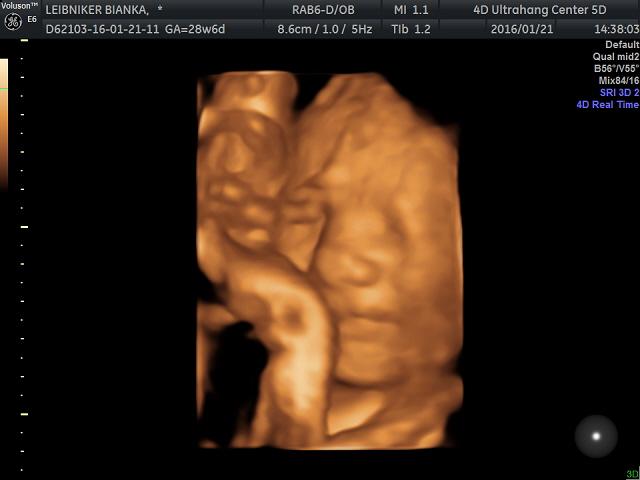

28. heti Uh Kép